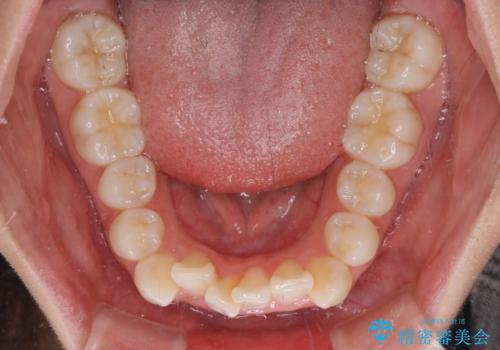

- 歯のデコボコや八重歯、クロスバイトを気にして来院された患者様です。

上下左右第一小臼歯4本を抜歯し、ワイヤー装置にて歯列を整え、さらには少しでも口元を引っ込めるよう矯正治療を行うこととしました。